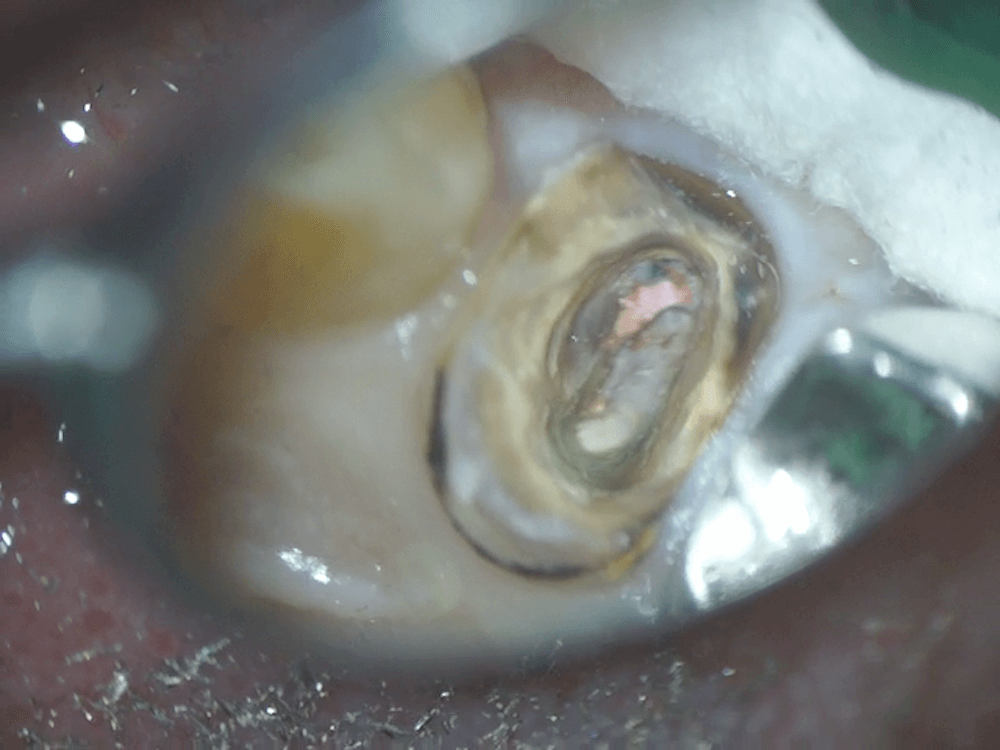

ポストを取り除いた後の写真です。ただでさえ歯の量が少なくなっている歯の余計な部分を削らずに、ポストを取り除くことができました。

このあと、通常の根管治療を行っていきます。